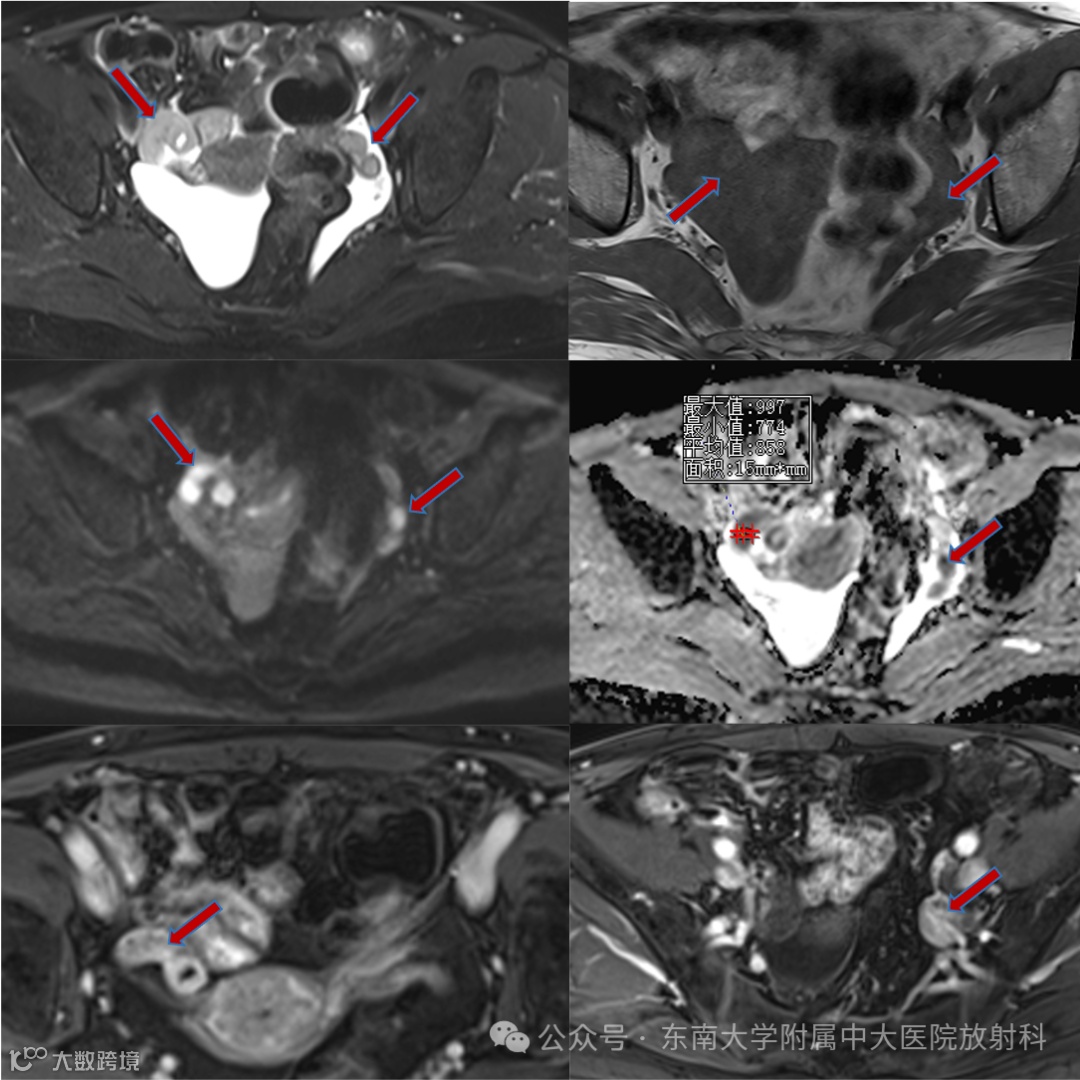

病例1

女,56岁 -

主诉:腹痛1月余 -

现病史:患者一月余前无明显诱因出现右上腹痛,伴有全身肌肉酸痛,自觉发热,体温未测,自行口服“白加黑”后全身酸痛好转,腹痛改善不明显,后口服“甲硝唑片”,腹痛稍有改善,深呼吸时加重,偶有头痛,食欲下降,遂至外院住院治疗,住院期间未予特殊治疗。现患者仍有上腹部疼痛,较前稍缓解,为进一步诊治来我院。患者无畏寒发热,无体重消瘦,否认“肝炎”、“结核”、“伤寒”等传染病史 -

实验室检查:

影像学表现